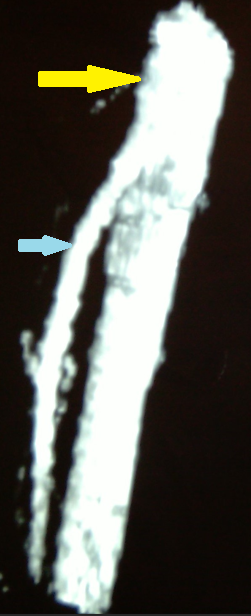

Purple arrow – Stomach. Green arrow – Aorta. Yellow arrow – Distance between the superior mesenteric artery and the aorta. Red arrow – Superior mesenteric artery. Blue arrow – Duodenum. Courtesy Dr. V. Penopoulos.